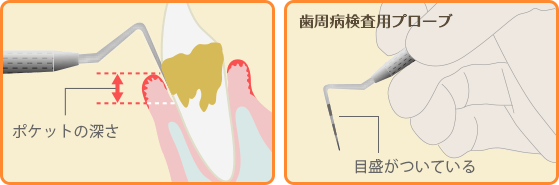

ポケット検査

「プローブ」という器具で歯と歯ぐきの間の溝(歯周ポケット)の深さを調べます。歯周ポケットが深ければ深いほど歯周病が進行しています。

歯周病検査の結果を基に、歯周病の進行状況に合わせた治療法をご提案いたします。

軽度の歯周病の場合、専門的なクリーニングや正しいセルフケアなどで改善することができますが、重度まで進んでしまった歯周病は、改善に時間がかかってしまうことがあります。

いきなり治療に入るのではなく、治療法や治療期間の説明をしっかりと行い、ご納得いただいてから治療に入りますのでご安心ください。